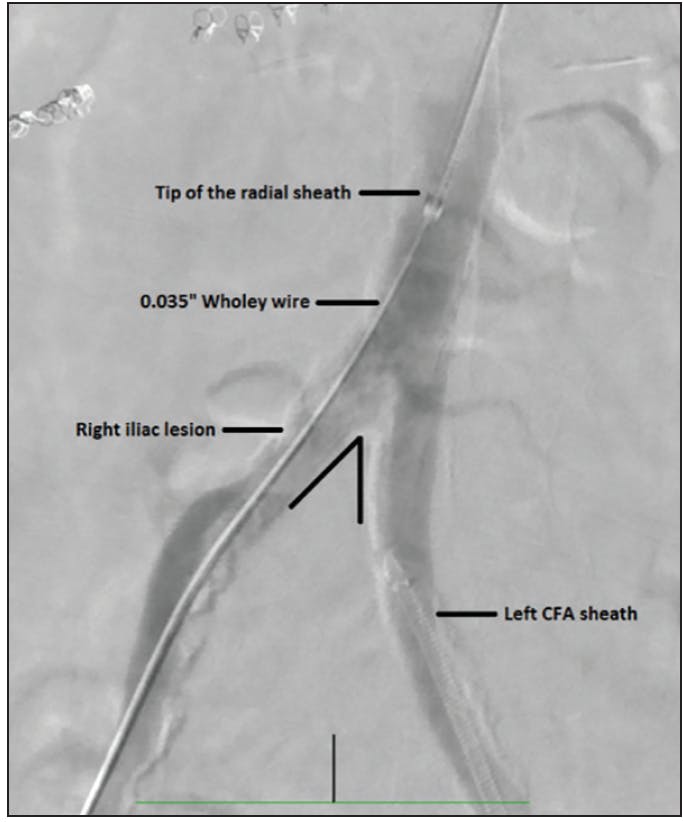

Difficulty in tracking the sheath over the wire is commonly encountered. The first step is usually to use a stiffer wire and advance it as far as it can reach. If it’s still a struggle, then apply constant pressure to advance the sheath while pulling the wire (the “paradoxical move” technique). If this does not work, then perform the “Dottering” technique by moving the wire gently backward and forward while applying constant forward pressure on the sheath to help decrease wire wall bias and center the sheath for easier advancement. If still unsuccessful, free the dilator from the sheath and walk the sheath over the dilator in small steps with a great amount of care to avoid vessel wall injury. Then, follow the sheath with the dilator and repeat walking the sheath over the dilator as needed. In extreme cases, the “balloon-assisted tracking” technique can be used. Inflate a balloon in the SFA or the profunda artery at a nominal pressure to stabilize the wire and create a strong rail over which the sheath can be advanced (Figure 1). An acute angulation of the abdominal aortic bifurcation can make wire and/or sheath advancement unfeasible despite all the previously mentioned maneuvers. In such a situation, special catheters such as a Simmons or SOS Omni can overcome this problem; however, these catheters need to be shaped in the aortic arch, and therefore heparinization is advised. The presence of kissing iliac stents makes crossover impossible, so radial access needs to be considered (Figure 2).2

Figure 2. Radial access for acute angulation of the abdominal aortic bifurcation. Note the acute angulation of the abdominal aortic bifurcation. An SOS or Simmons catheter may have performed well in crossing over. However, in this patient, we choose to proceed with radial access because there was also a significant ostioproximal right iliac lesion that needed treatment. After achieving right radial access, we crossed into the right iliac artery using an 0.035-inch wire with the help of an IM catheter. Then, a long 6-F, 119-cm R2P radial sheath (Terumo Interventional Systems) was introduced into the distal abdominal aorta over the Wholey wire.